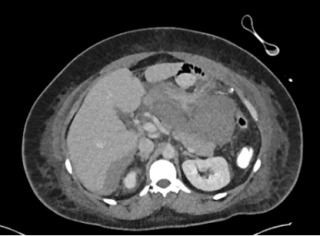

An 82-year-old otherwise healthy man was referred for evaluation of an incidentally detected left adrenal mass. The patient was asymptomatic with no clinical signs of catecholamine excess, hypercortisolism, hyperaldosteronism or B-symptoms. Initial CT scan revealed a 44 × 42 mm lesion, which increased to 50 × 46 mm within three months and suspicious washout characteristics (Figure 1). Endocrinological work-up showed a pathological dexamethasone inhibition test, while metanephrines and aldosterone testing was normal. Tumor markers (AFP, β-HCG) were unremarkable. A hormonally active adrenal adenoma with autonomous cortisol production was suspected.